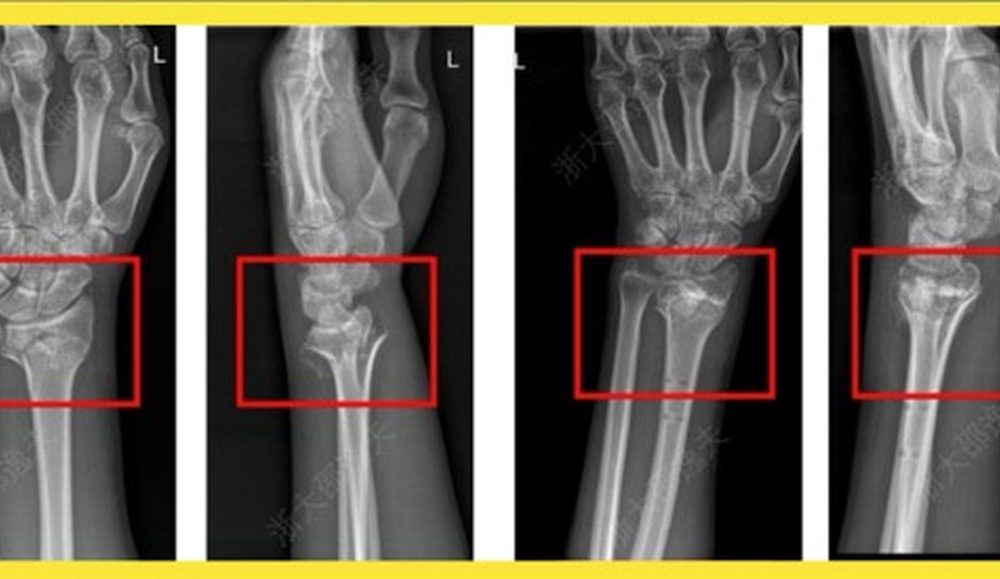

Em caso experimental, um paciente com fratura no punho recebeu uma injeção através de uma incisão de apenas 3 cm e foi curado em apenas três...